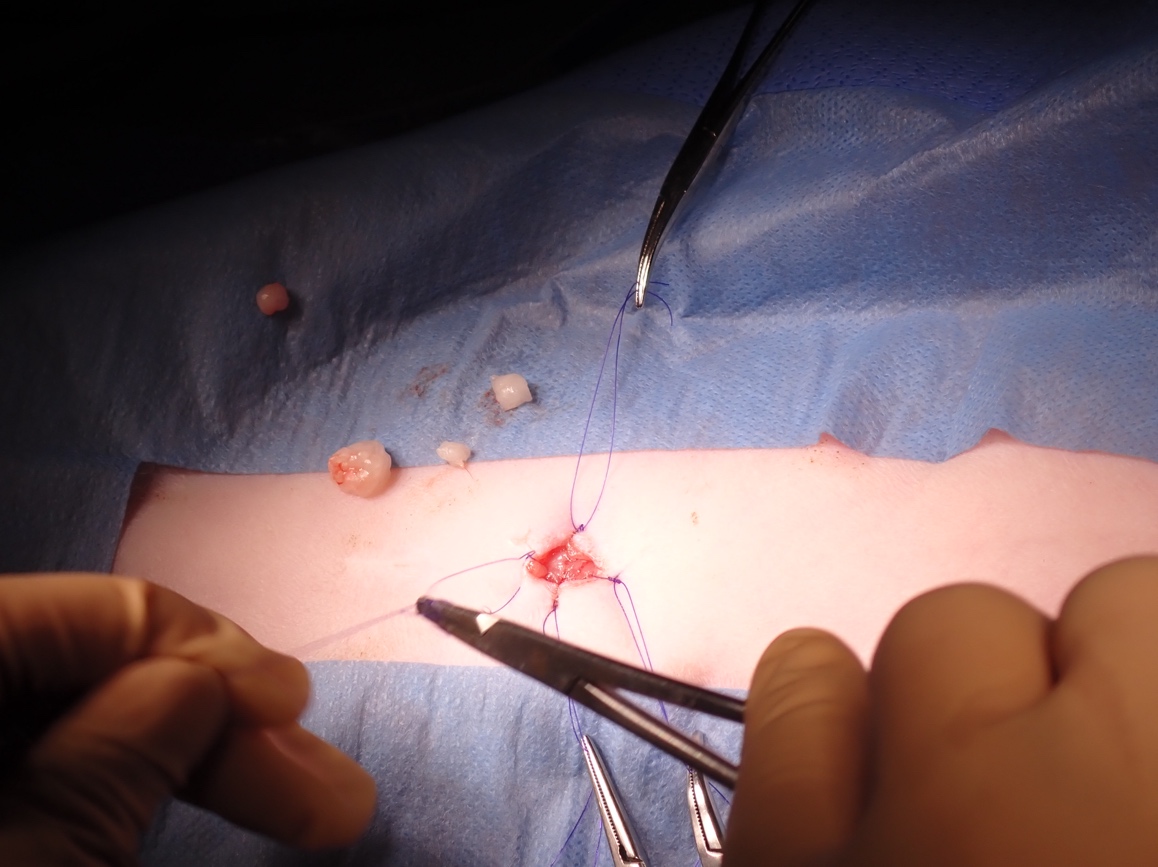

1cm程度の切開を加え糸で膀胱を釣り上げてからカメラを入れる筒を入れる様子

手術の全体像